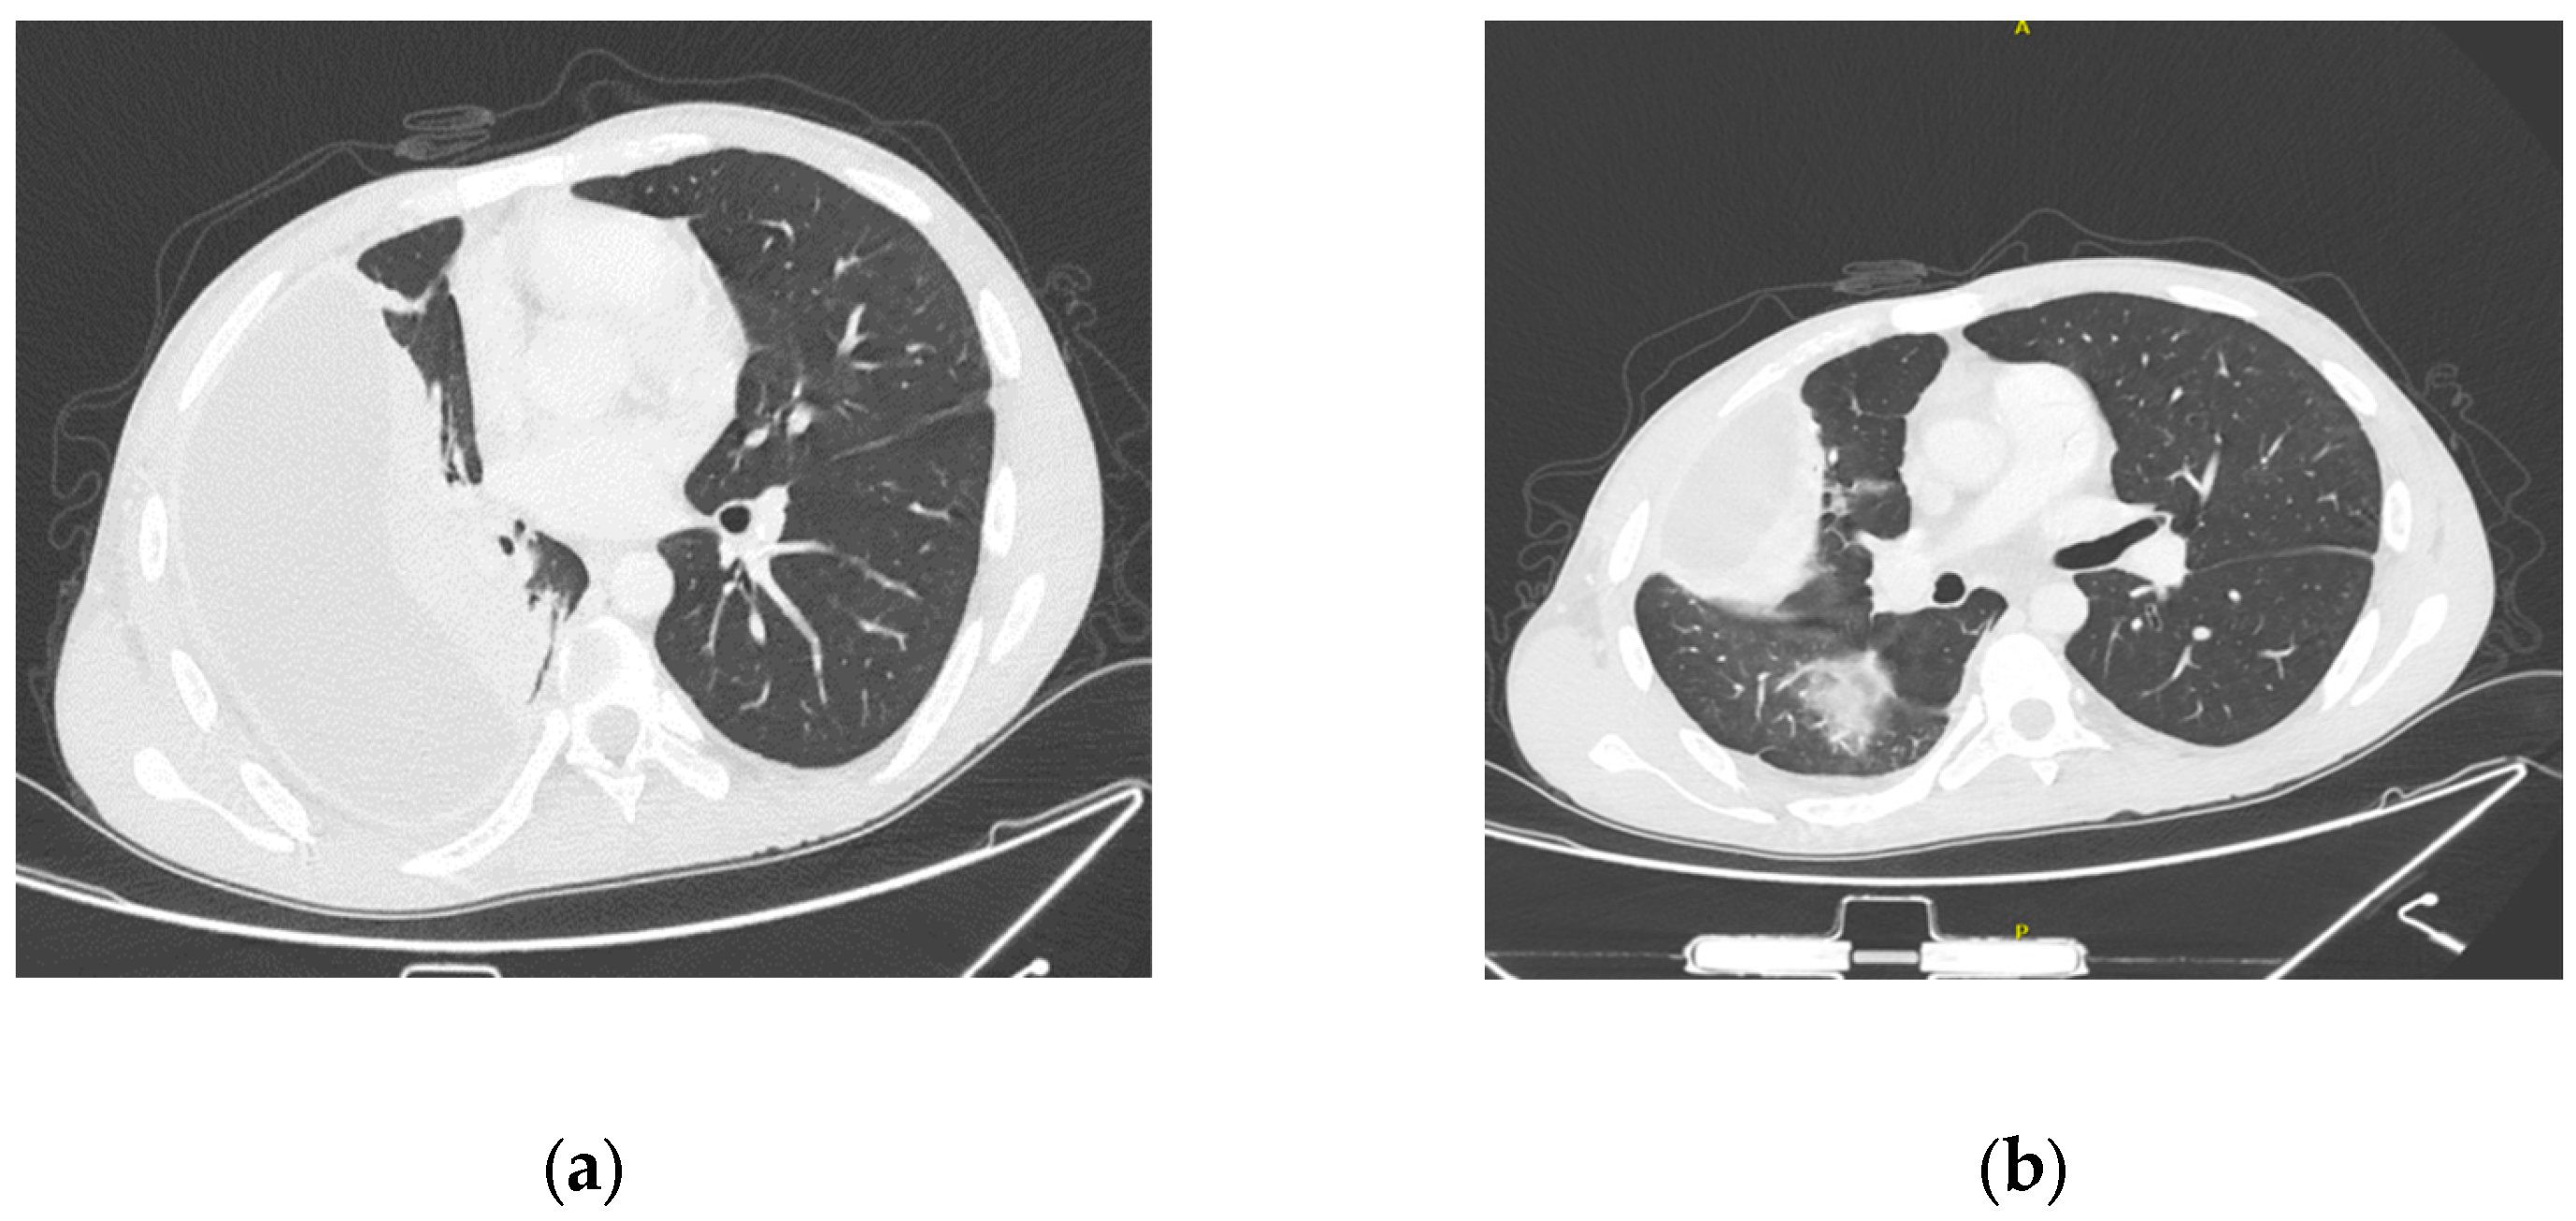

2. Literature Search

3. Case Report